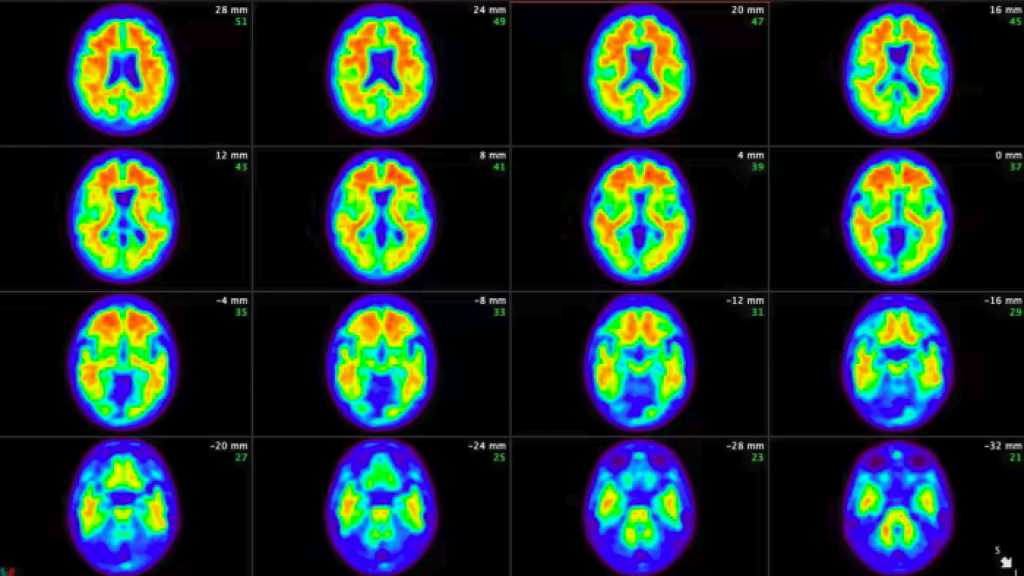

Both lecanemab and donanemab are based on antibodies against amyloid, one of the toxic proteins that build up in the brain as Alzheimer’s proceeds, but they worked at different stages of the process, Oakley said.

Lecanemab targets amyloid as it begins to form fibers in the brain while donanemab is active at a later stage, when the fibers have clumped together into larger accumulations of plaque. The main adverse side effect of both drugs was swelling and bleeding of the brain in a small minority of patients.

It cleared amyloid plaques completely from the brain in some participants, who were then taken off the drug.